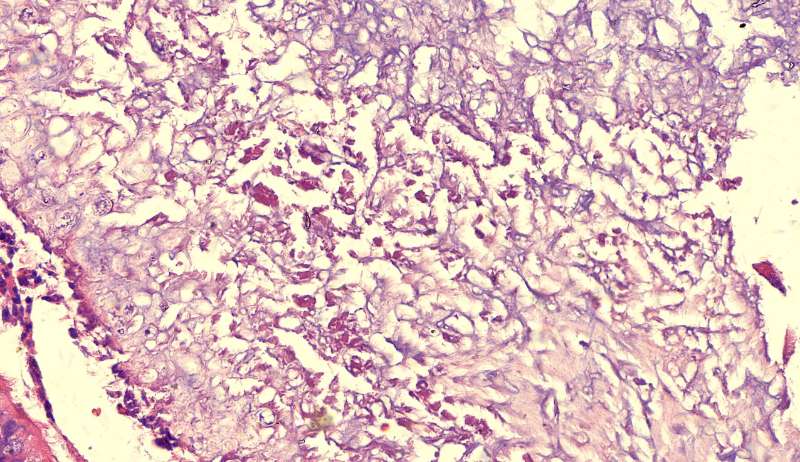

隐球菌

结节状,周围型,宽基底,巨噬细胞多而且大,有纤维组织,所以经常有点收缩力

这些就是隐球菌,常被巨噬细胞吞噬,大多为多核巨噬细胞 隐球菌感染,在免疫力正常情况下,就是个肉芽肿 小白球,略显淡蓝色,这是荚膜的感觉

隐球菌在HE染色是小白球,隐隐的,球状的。在PAS染色是红色的小球,在六铵银染色是黑褐色的小球。

第二例隐球菌

整体是个类圆形,边界模糊(有晕征的感觉),肉芽肿一般都这样 里面也能见到许多小白球,大小从3微米到20微米不等 红细胞直径5-6微米 普通小淋巴细胞直径5微米 这里淋巴细胞挺多 有许多淋巴细胞,成堆

多核巨噬细胞吞了许多隐球菌 经常是反包围的感觉

这三幅是周围区,也有巨噬细胞,单核的多 都在肺泡腔内 所以有ggo样密度 过一段时间,晕就消失,有时是消退,有时是实性区扩大,盖住磨玻璃晕 那也是吞噬的作用,常代表免疫力正常 就是警察多了把肺泡填了